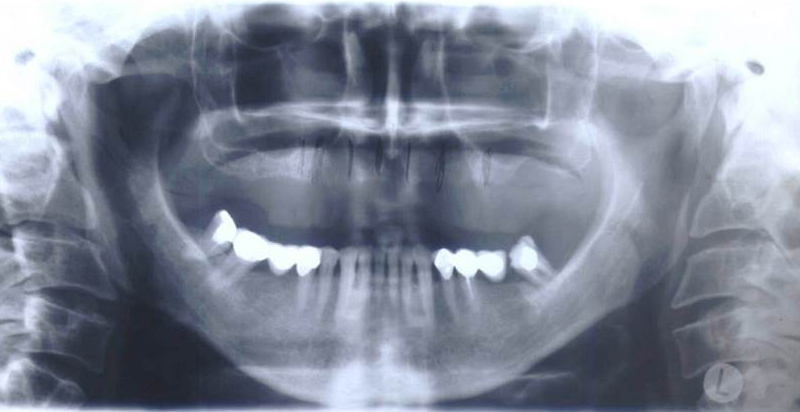

Při ztrátě molárů a premolárů v horní čelisti a jejich náhradě implantáty se často setkáváme s nedostatečnou vertikální nabídkou kosti pod čelistní dutinou, často doprovázenou i nedostatečnou horizontální nabídkou a sníženou kvalitou kosti

(v oblasti 2. premoláru v 50%, v oblasti moláru až v 80% případů nedostatečná kostní nabídka)